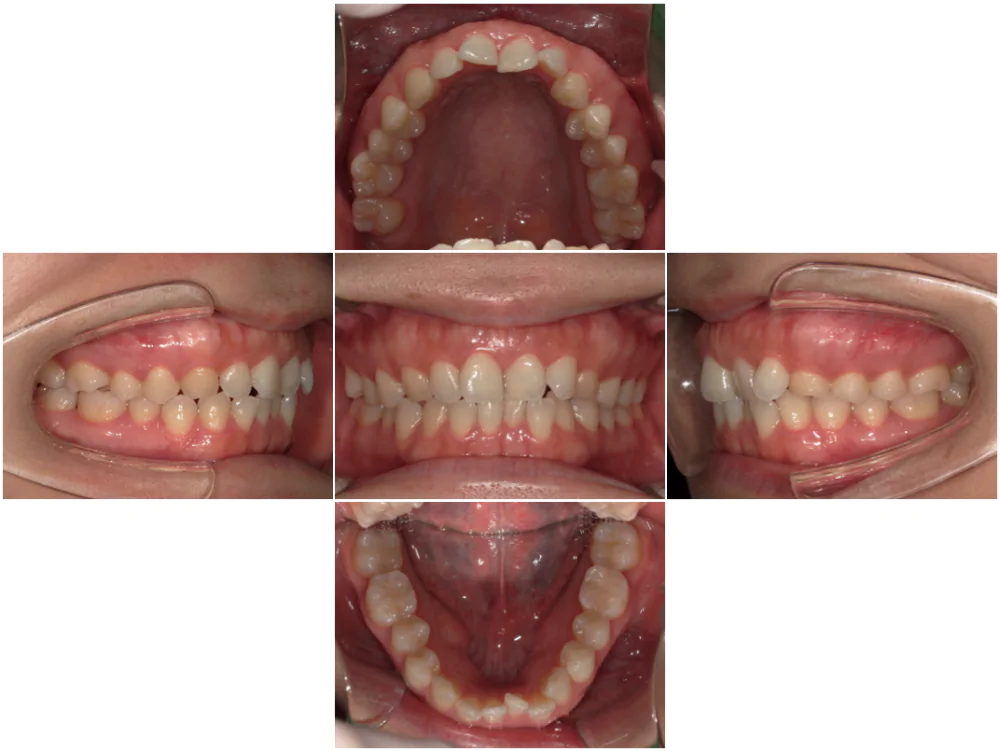

症例1

| 来院時の主訴 |

全体的なガタガタを治したい。

できれば抜歯はしたくない。

歯並びを気にせず笑えるようになりたい。

| 医院での対応や適用装置 | マウスピース矯正装置を使用して主訴であるガタガタを改善しました。 ガタガタの改善に必要なスペースの確保のために上あごの親知らずのみ抜歯を行いました。 |

| 通院期間 | 1年1ヶ月 |

| 通院回数 | 7回(治療中) |

| 治療費用総額 | 725,000円(税込) |

| リスクと副作用 | 矯正治療による歯の移動に伴う痛み、歯根吸収、虫歯 |